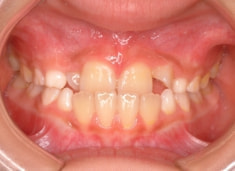

小児期ケース:反対咬合+上顎両側3番埋伏歯

(受け口+3番目の永久歯が左右両方とも埋まってしまい、はえてこない)

治療前